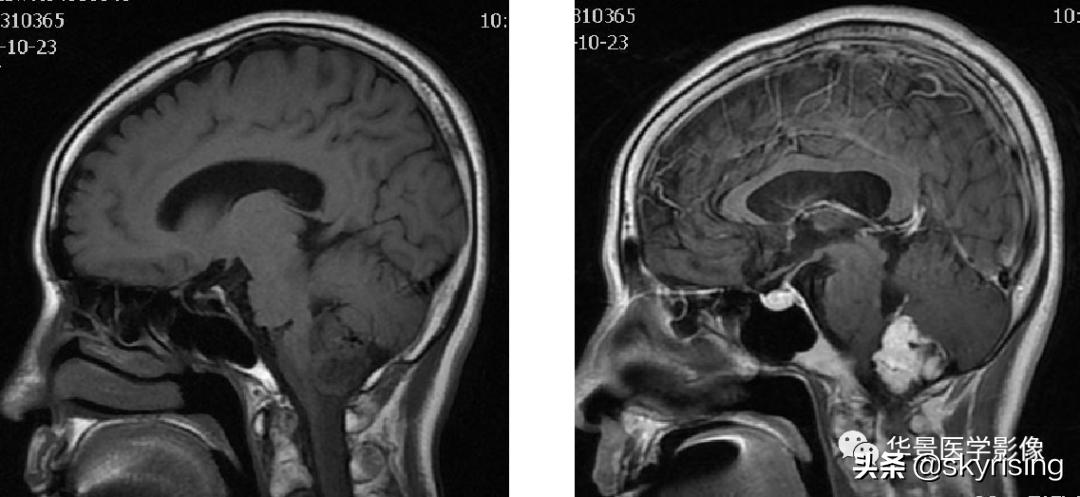

上图白色箭头:小脑延髓池内延髓背侧不规则形团块影,小脑半球、延髓、第四脑室受压变形,所见诸脑室未见增宽。

上图白色箭头:病灶呈DWI低信号,ADC高信号,信号欠均,提示弥散不受限。

小脑延髓池内见不规则异常信号影,呈长T1长T2信号,内部信号不均,边缘见稍粗大流空信号血管影,FLAIR少许片状低信号,增强呈明显强化,DWI不均质低信号,ADC不均质高信号。小脑半球、延髓、第四脑室受压变形。临近延髓变窄,呈长T1长T2信号。